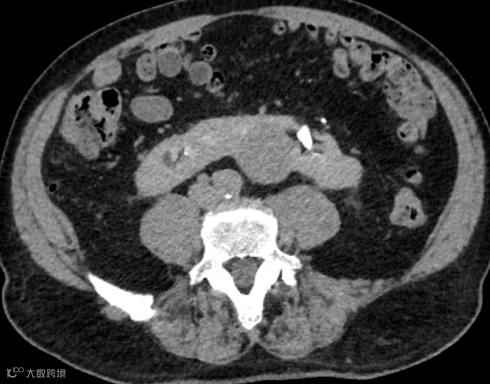

女,25岁,马蹄肾。肾脏下极相连,呈马蹄形,肾皮质厚度正常,泌尿系统未见梗阻扩张。